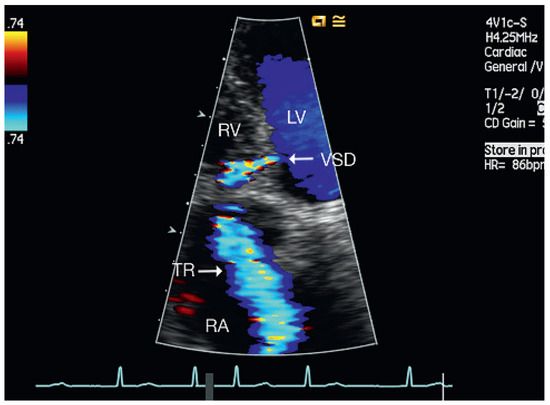

Muscular Ventricular Septal Defect After Mitral and Aortic Valve Replacement

by Augusto Aragão, Dorothea Vogel and Christoph Schmidt

Cardiovasc. Med. 2010, 13(5), 167; https://doi.org/10.4414/cvm.2010.01500 - 26 May 2010

We describe a case series of five patients who were referred to our cardiac rehabilitation department after mitral or aortic valve replacement, and whose transthoracic echocardiographic studies showed postoperative muscular septal defects. Full article

Show Figures

Figure 1